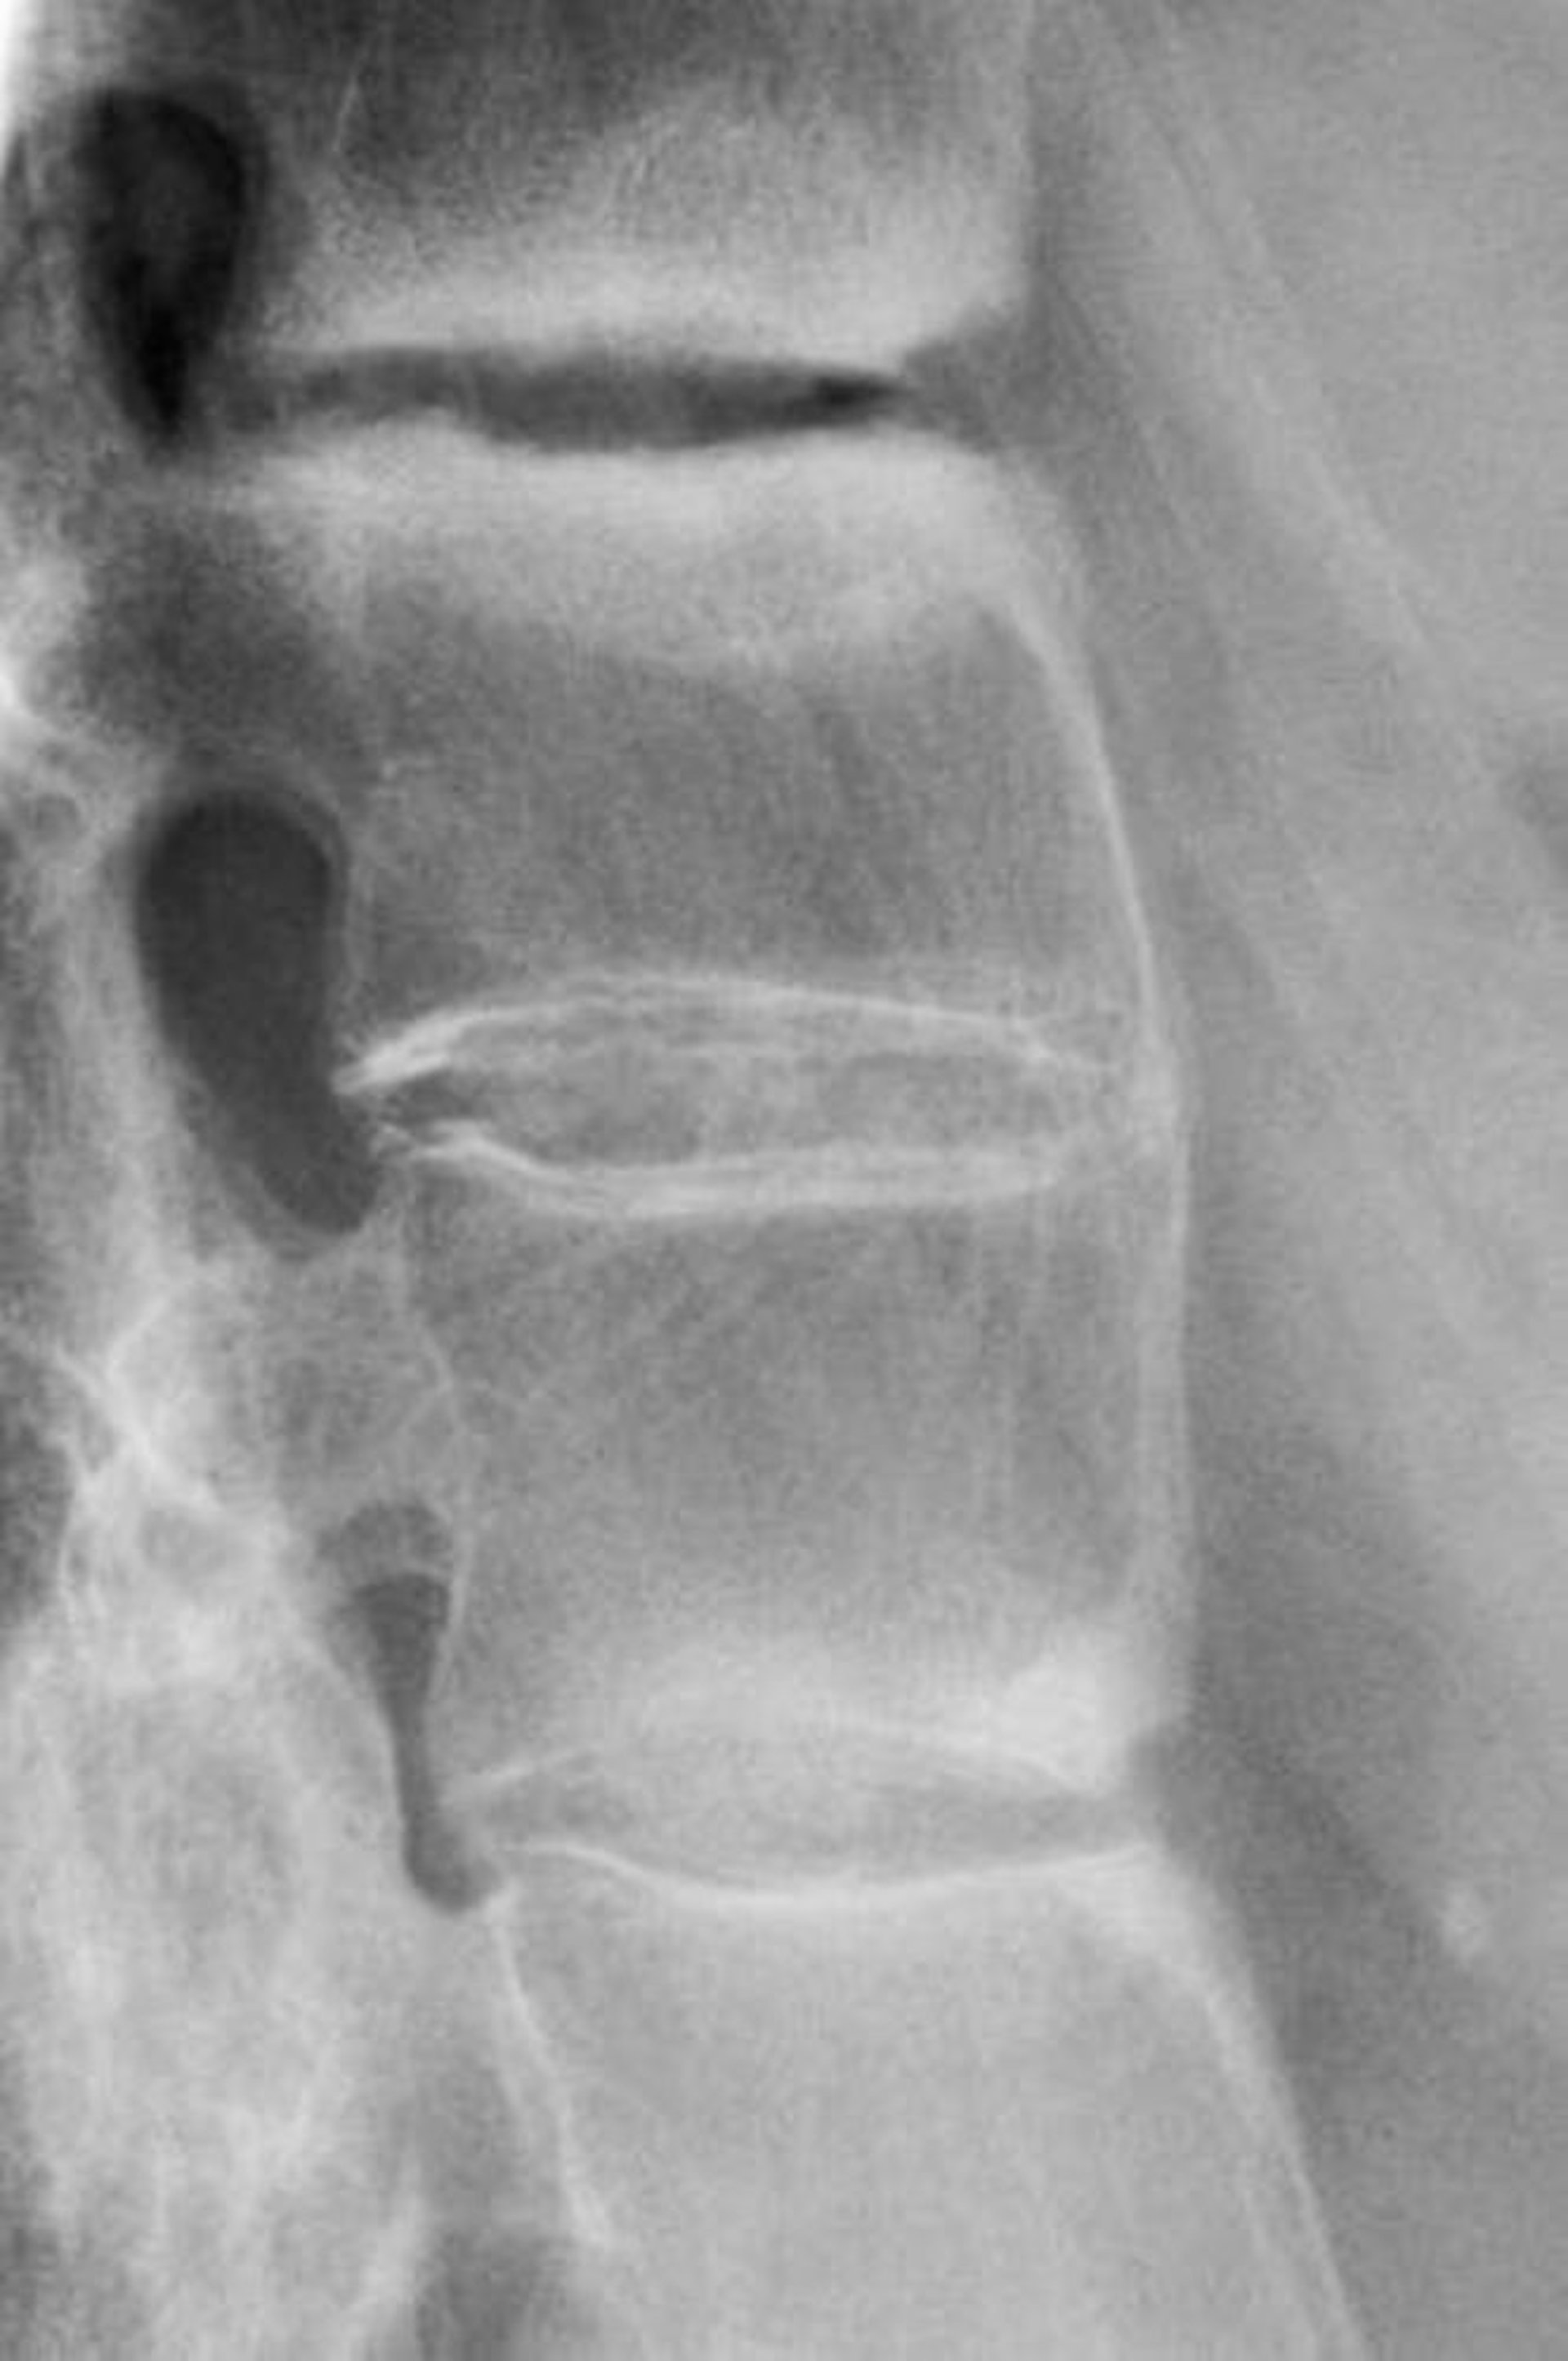

Viêm cột sống dính khớp

Phim X-quang này cho thấy xơ cứng giữa các đốt sống thắt lưng, mất độ ưỡn và dính các đốt sống thắt lưng, một dấu hiệu cho thấy viêm cột sống dính khớp giai đoạn tiến triển.

BÁC SĨ P. MARAZZI/THƯ VIỆN HÌNH ẢNH KHOA HỌC